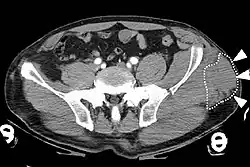

Computed tomography

Computed tomography (CT) is important in settings of an emergency or when magnetic resonance imaging is not available.[8] CT will show the presence of a Morel-Lavallée lesion and whether fluid is present.[7] The use of contrast can also help determine if fluid present in a lesion is due to active bleeding.[8]

The diagnosis of a Morel-Lavallée lesion can be made based from clinical observations or medical imaging. Imaging can confirm a diagnosis or detect an injury that was not clinically apparent. Morel-Lavallée lesions can be detected with several types of medical imaging. Each one has its own benefits and limitations. A lesion can be distinguished as acute or chronic based on features present in the imaging. Computed tomography is often the first imaging used in diagnosis.[7] This is because computed tomography is often the first imaging done for patients with traumatic injuries.[7] Magnetic resonance imaging is generally the imaging of choice for obtaining well-defined imaging of the lesion.[5][6] More information on the types of imaging that can be used are discussed below.